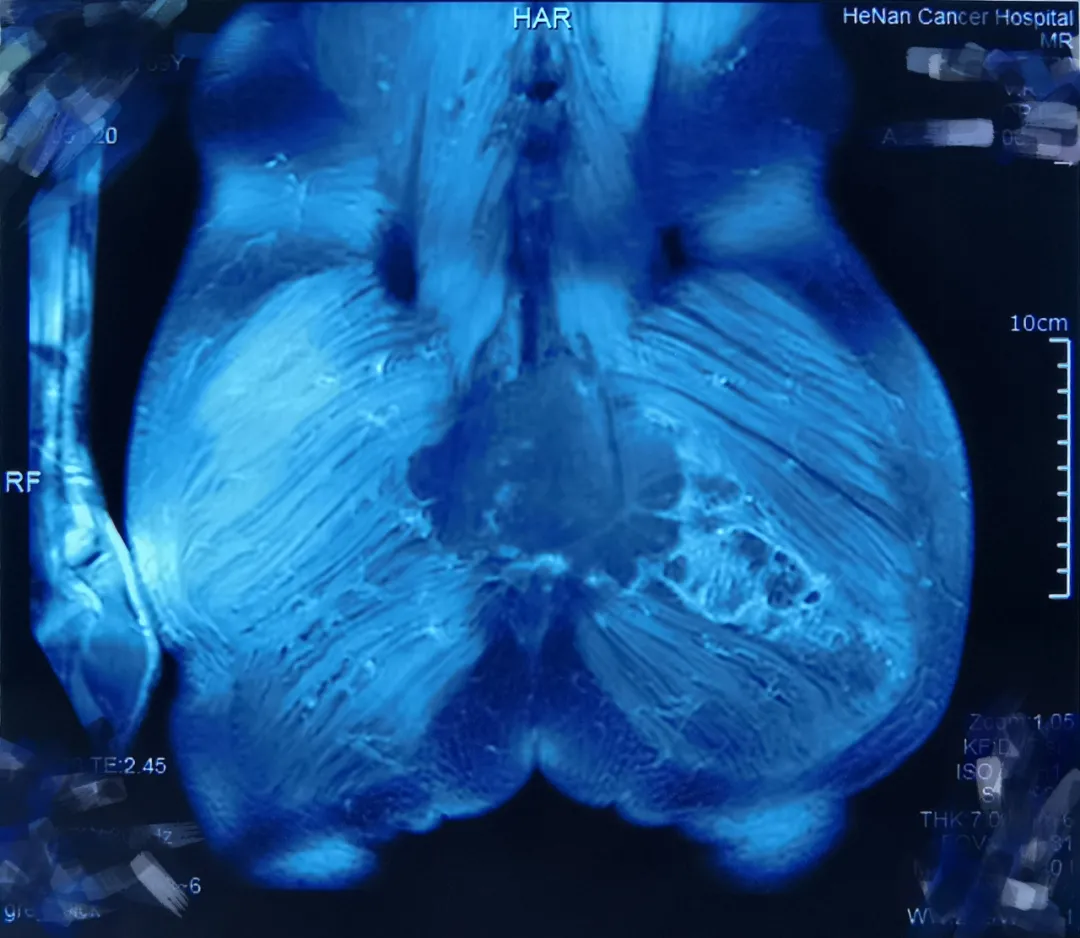

由于肿瘤大,手术创伤面也很大,王家强巧妙利用残存的臀大肌组成皮瓣进行创面修复。

![]()

经过4个小时的精细手术操作,术后护理确定皮瓣成活,大小便及双下肢功能正常。10天后,李老先生顺利康复出院。